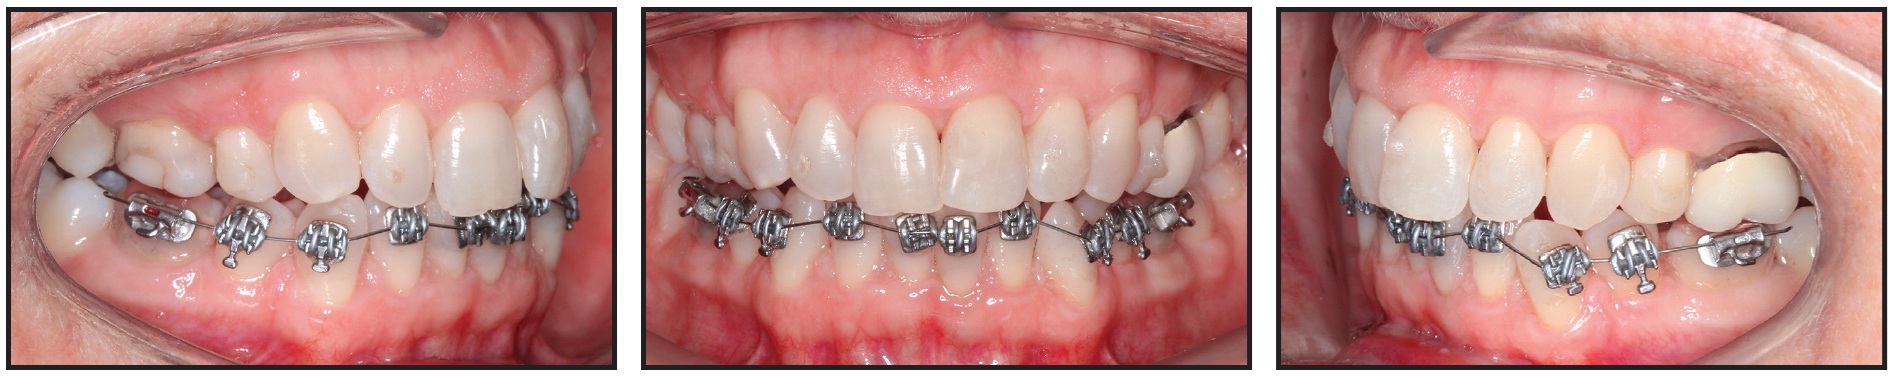

The most common form of hybrid aligner treatment combines upper clear aligners and lower full-arch labial appliances (Fig. 1). This approach is typically employed in an adult patient with a deep overbite and excessive lower curve of Spee, especially in the presence of preexisting mandibular spacing. Such a patient benefits from a strong reverse-curve archwire throughout treatment to open the bite and intrude the lower incisors, while the upper clear aligners provide the necessary occlusal protection.1

Fig. 1 Lower full-arch labial appliance for use with upper clear aligners.